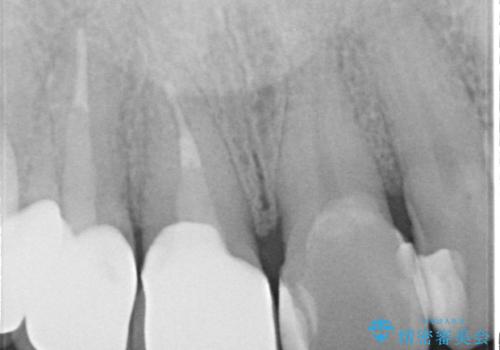

- 以前治療した上の前歯の不自然な保険のかぶせ物を自然なものにしたいとのことで来院されました。

右上の前から1番目から3番目までの歯のかぶせ物を土台から再治療することとなりました。

金属の土台を、ファイバーコアという歯根にやさしく白いものに交換して、かぶせ物をオールセラミックにしました。